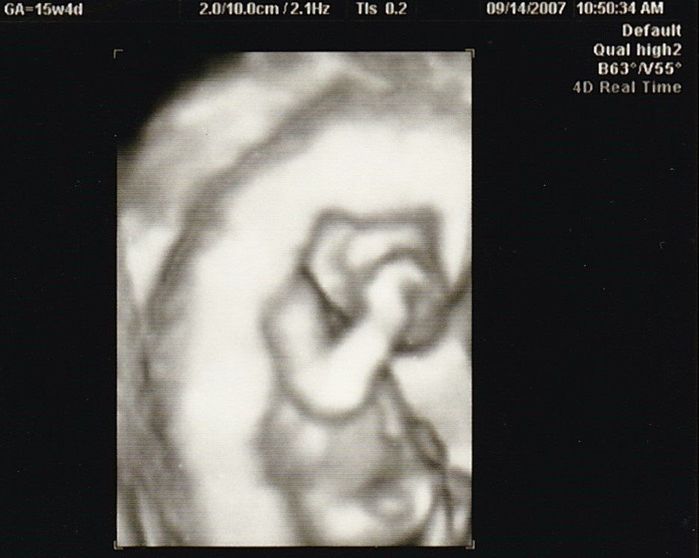

妊娠15週目のエコー写真

やっと安定期に入りました。「性別は、次回の検診のときに聞きたければ教えますよ」と言われていて、今回“男の子”と教えてもらいました。手で目をこすっているような様子など、かわいいな、早く会いたいな、名前どうしようかな、と思いを巡らせていました。退職したため、夫の休みに出産前最後の旅行もしました。